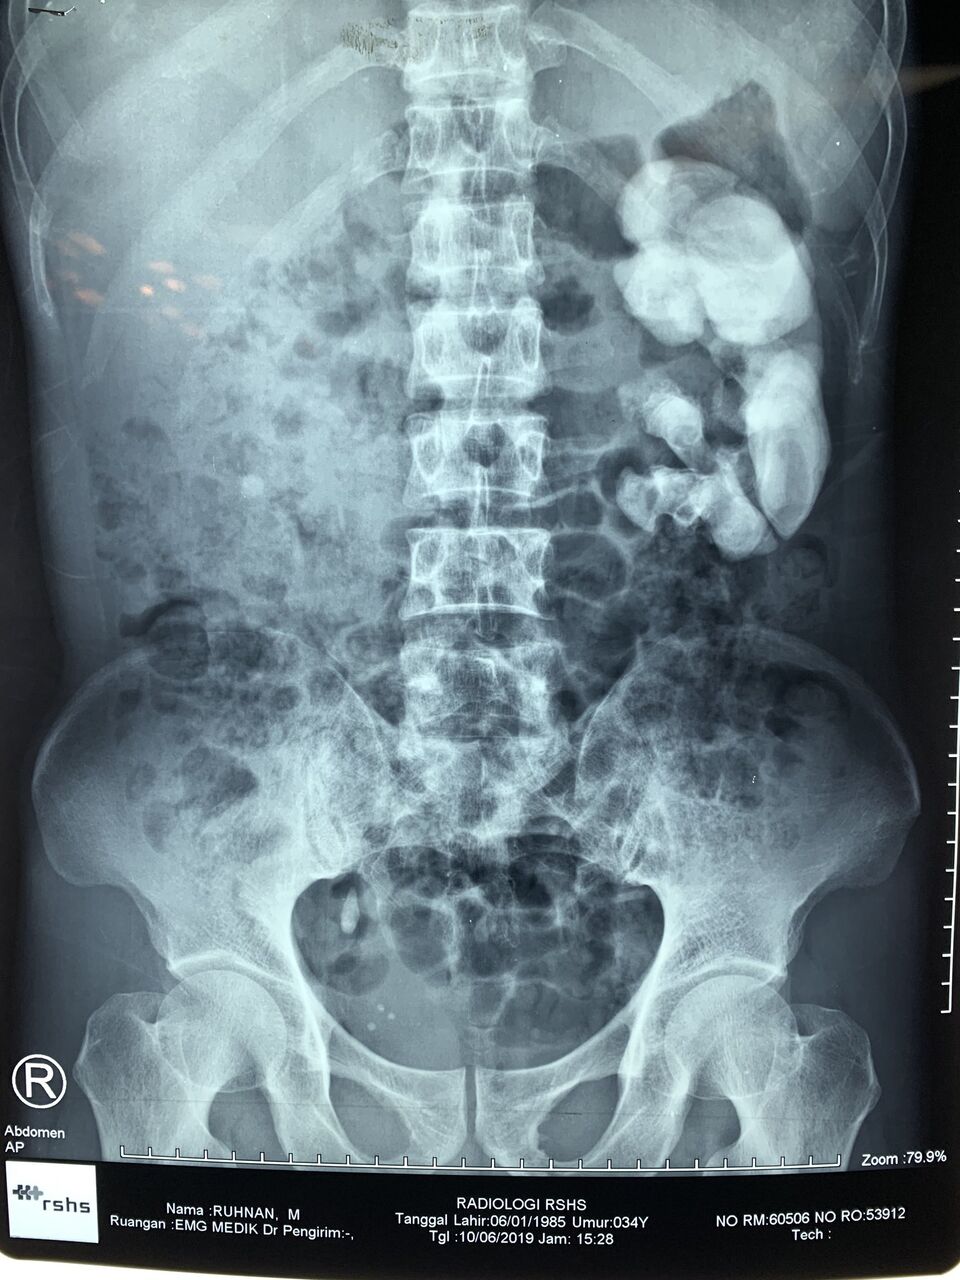

こんなの尿道から出たら死んでまう!

正体はシュウ酸カルシウムだったかな

結石が出るのが痛いんじゃなくてこいつが詰まって膀胱がパンパンに膨れるのが痛いんだよ

勘違いする奴多いけど、このトゲトゲが通るのが痛い訳じゃないんだ

トゲトゲで尿路を塞いでそこにパンパンに尿が貯まってくると尿路が震えて周りの神経を揺さぶって激痛になるんだ

金玉を蹴られた痛みが絶え間なく続くと思ってくれ

結石

歯に見えた